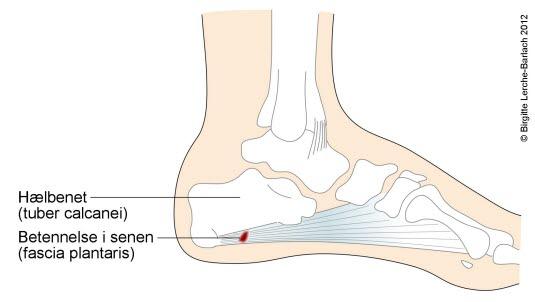

Plantar fasciitt (plantar hælsmerte) er hælsmerter som stråler fremover foten. Dette er en betennelse i fotsålens seneplate der den fester seg til hælbenet. Tilstanden gir smerter når du tråkker ned på hælen.

På undersiden av foten har vi en seneplate som kalles plantarfascien. Den har utspring fra forkanten av hælbenet (kalkaneus) og brer seg i vifteform frem til tærne. Fascien sørger for optimal fot-biomekanikk i forbindelse med avviklingen av steget - hællanding, flat fot og fraspark. Plantar hælsmerte eller plantar fasciitt som tilstanden heter på fagspråket, er en tilstand hvor plantarfasciens feste til hælbenet er overbelastet og irritert.